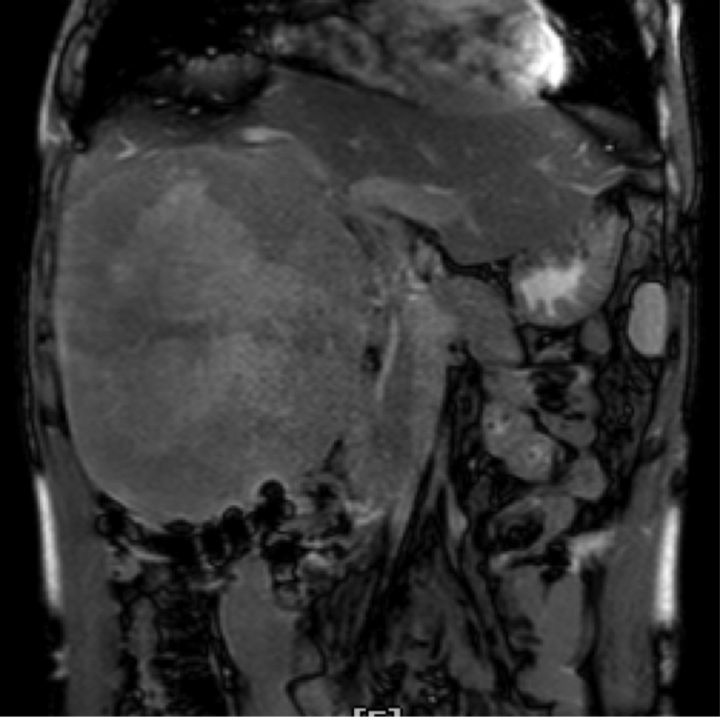

原来,此前意识到身体可能出现问题后,陈先生立刻到当地医院做了检查,诊断结果显示,他的右肝长了一个“足球大小”的巨大肿瘤,且该肿瘤紧贴肝脏大血管,手术风险极大。

温医大附一院肝胆外科在复杂肝癌的外科手术治疗方面有许多成功经验,肝胆外科主任余正平主任医师、副主任陈钢主任医师团队随即为陈先生开展诊治。团队接诊后发现,陈先生的右肝长的巨大癌肿,大小约210mm×160mm×130mm。不过万幸的是,他们测量到陈先生剩余肝脏的体积占其标准肝脏体积的40%左右,可以满足肝脏正常生理功能,且无肝内外转移。

手术切除下来的肝肿瘤